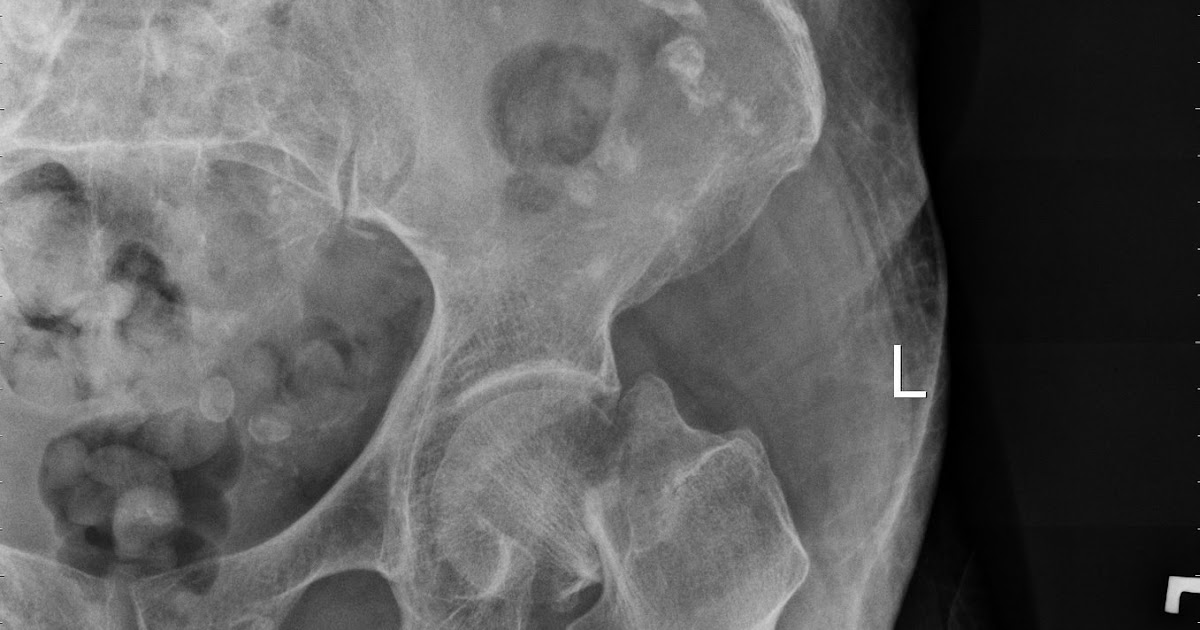

Garden described particular femoral neck and acetabular. White line of increased density of impacted bone may be seen at base of femoral head. Garden classification of femoral neck fractures it is important for management options and prognostic reasons to classify femoral …

Usually the person cannot walk. Fracture distal to articular surface & proximal to extend the hip while gently increasing traction. Subcapital fracture radiology reference article radiopaedia org. The garden classification for subcapital hip fractures is unreliable. Then internally rotate it to 30 to 45° in full extension. Learn vocabulary, terms and more with flashcards, games and garden classification. Hip fractures put the elderly at risk due to lower bone/muscle density, concomitant conditions, long recovery time, and hip surgery recovery complications. It is simple and predicts the development of avn 1,2. A hip fracture is a break that occurs in the upper part of the femur (thigh bone). As the population of older adults increases worldwide so too does the number of hip fractures. The total incidence was 1.32 fractures per 1,000 inhabitants per year. Partial/ incomplete fracture, trabecular alignment : Garden described particular femoral neck and acetabular. Conclusion the garden classification for subcapital hip fractures is unreliable and should be abandoned in favour of categorizing fractures as stable versus unstable. A hip fracture is an injury that typically only affects people over the age of 65. Relatively young patients (either chronologically or more important, physiologically) should have. It is simple and predicts the development of avn 1,2.